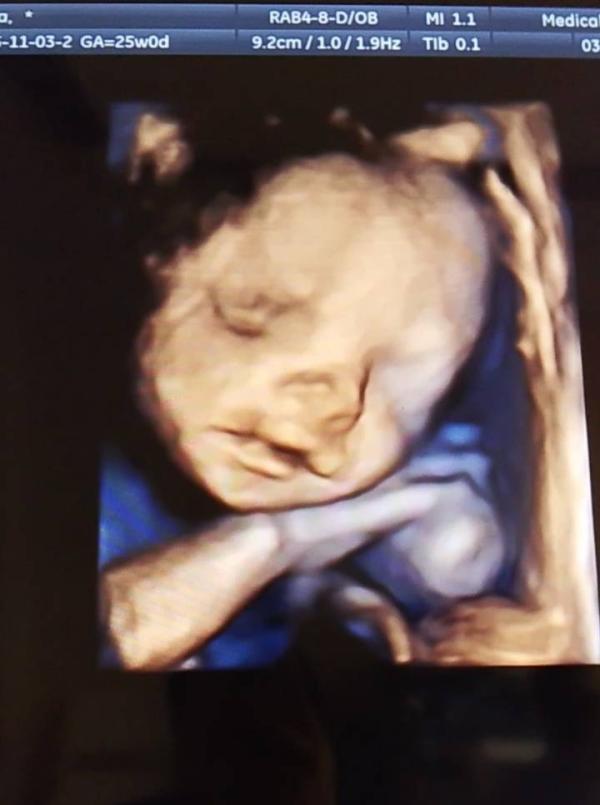

3-4D УЗИ при беременности: как прошло обследование

Ездили сегодня на 3-4D узи, с малышом все хорошо. Развивается по сроку.

Шустрый конечно, не давал себя мерить, и смотреть сердечко, но мы справились 💞💞💞